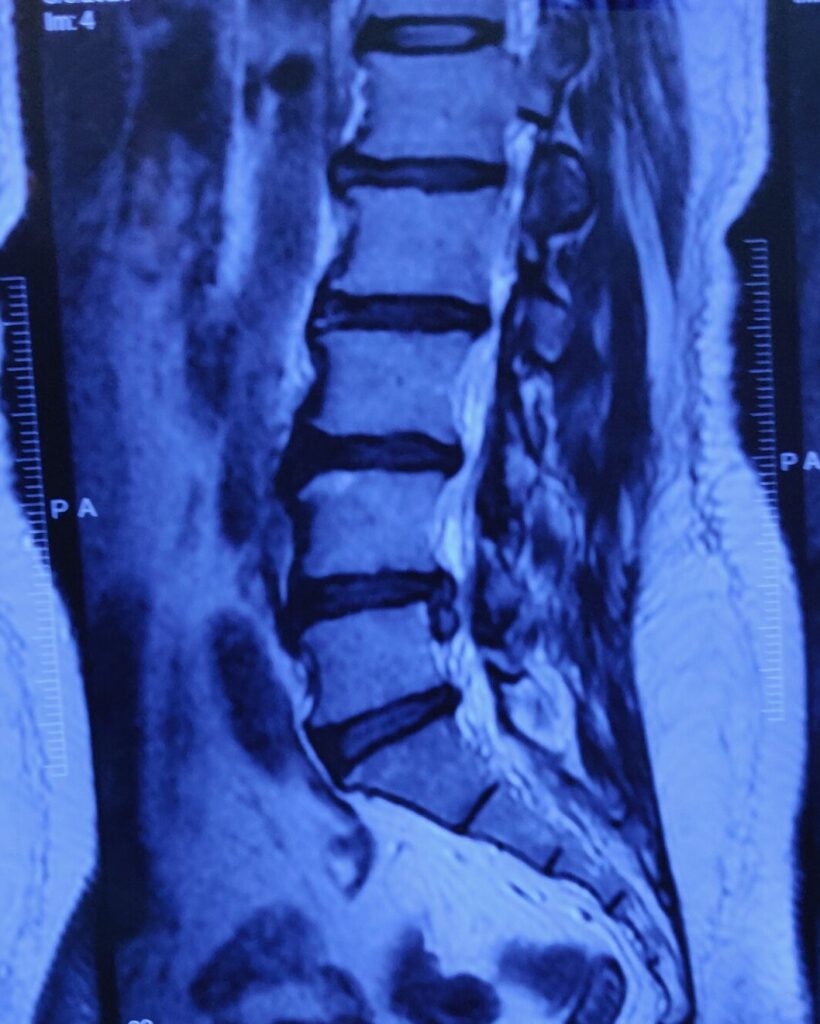

l4/l5 disc prolapse

lumbar disc Removed through endoscopy